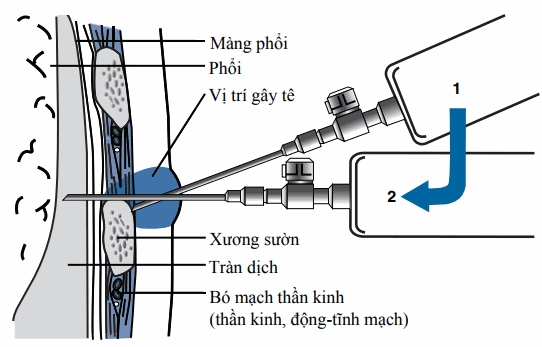

- Tràn dịch màng phổi không rõ nguyên nhân.